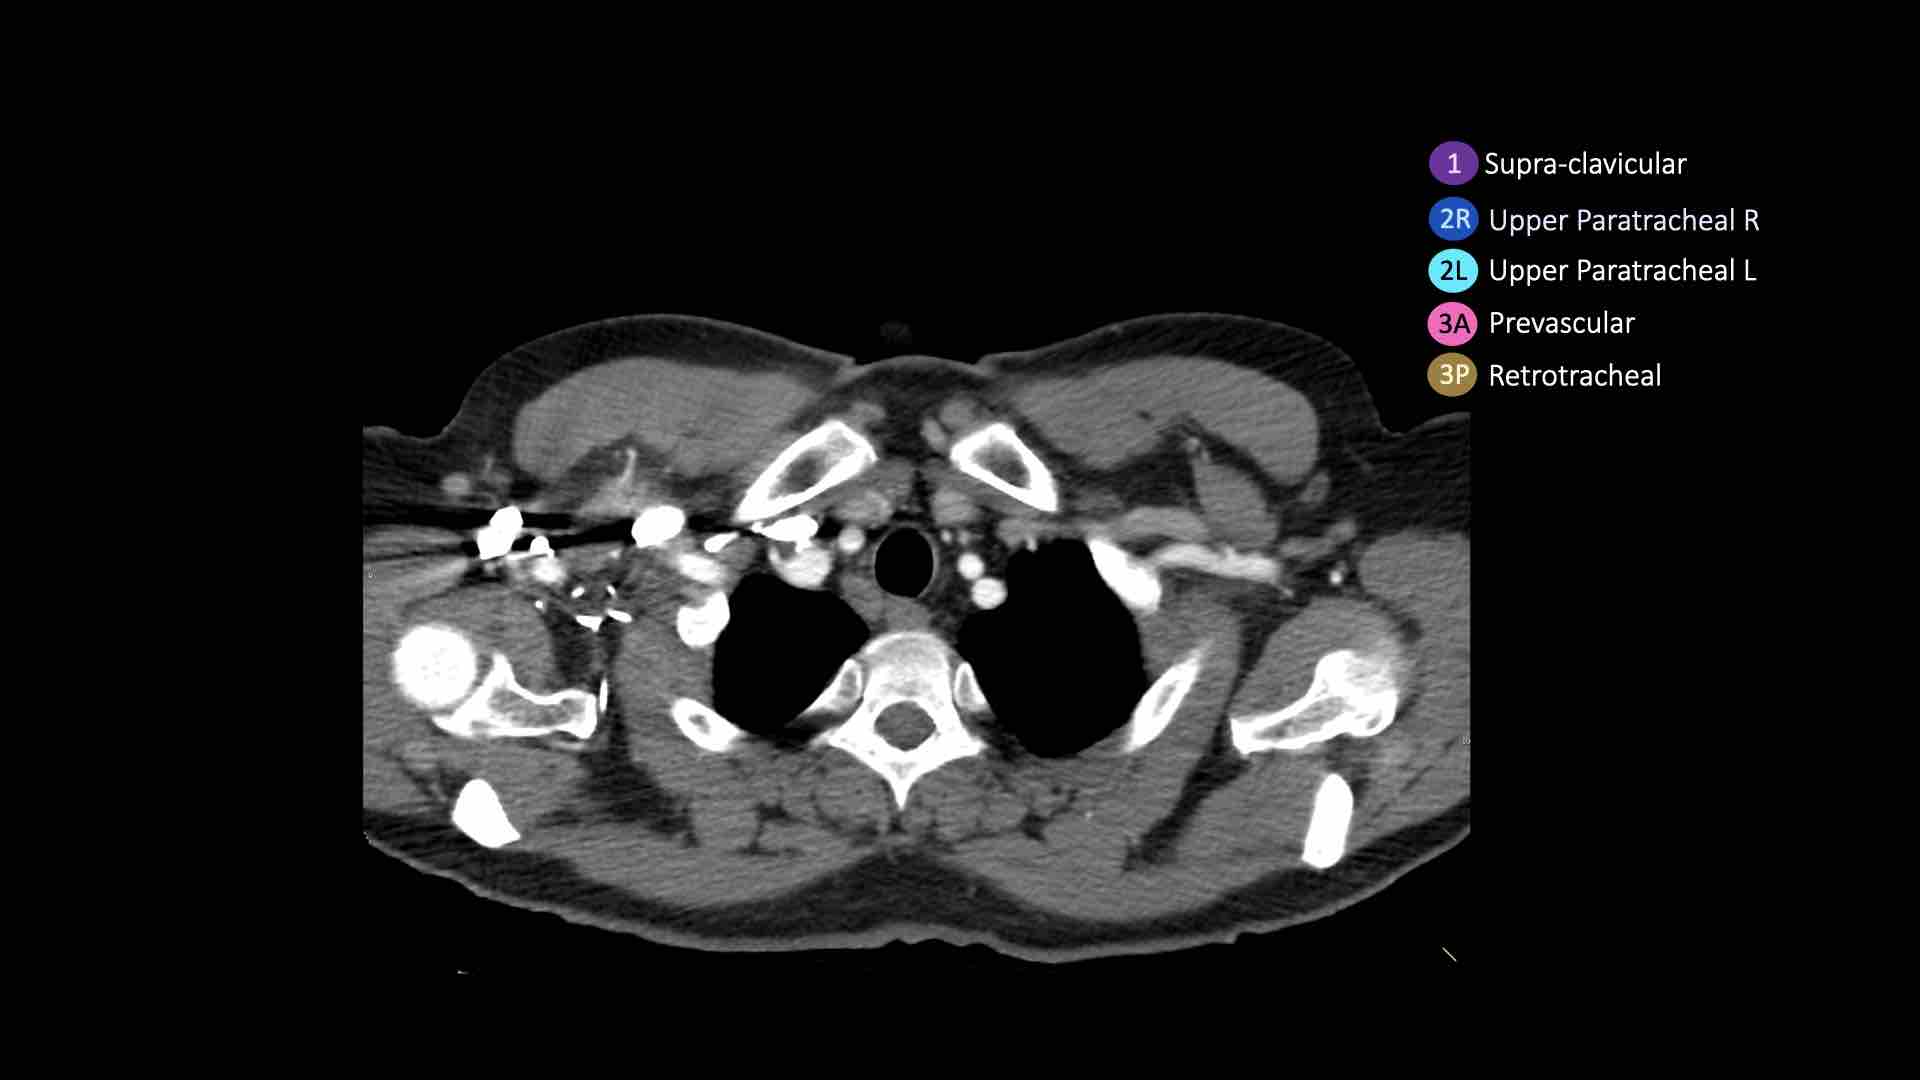

Giải phẫu CT cắt ngang

Nhấp vào hình ảnh để phóng to.

Sau đó cuộn qua các ảnh CT cắt ngang.

Hình ảnh do Bác sĩ Aurelia Fairise thuộc Viện Ung thư Lorraine tại Nancy cung cấp.

- Hạch bạch huyết khuyết ức có thể quan sát thấy ở mức này và phía trên mức này

- Cạnh khí quản trên: phía dưới xương đòn, bên phải nằm trên giao điểm của bờ dưới tĩnh mạch vô danh (tĩnh mạch tay đầu trái) với khí quản, bên trái nằm trên cung động mạch chủ

- Trước mạch máu và Sau khí quản: nằm trước các mạch máu (3A) hoặc trước cột sống (3P)